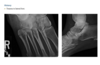

Foot pain

A

A lateral radiograph of the left foot demonstrates a prominent talar beak

­ (arrow) and bony sclerosis overlying the middle

facet (arrowheads). Coronal CT through the middle

facet shows talocalcaneal fusion, with bony bridging between the talus and the sustentaculum tali of the

calcaneus

Diagnosis: Tarsal coalition

abnormal fusion

of one or more of the tarsal bones, may be fibrous,

cartilaginous, or osseous and may be posttraumatic, or congenital.

Most

common tarsal coalitions are calcaneonavicular and

talocalcaneal.

Radiographically, calcaneonavicular coalition may

be suspected because of elongation of the anterior

facet of the calcaneus on radiographs (i.e., anteater

sign. CT can also be used to confirm coalition and shows

­ sclerosis at the articulation

Congenital coalition usually evolves from fibrous to osseous

coalition and may not be apparent on the initial

evaluation

Talocalcaneal coalition can result in dorsal beaking

of the talar head (Fig. 2.3.6, arrowhead), the so-called

C-sign (arrows)